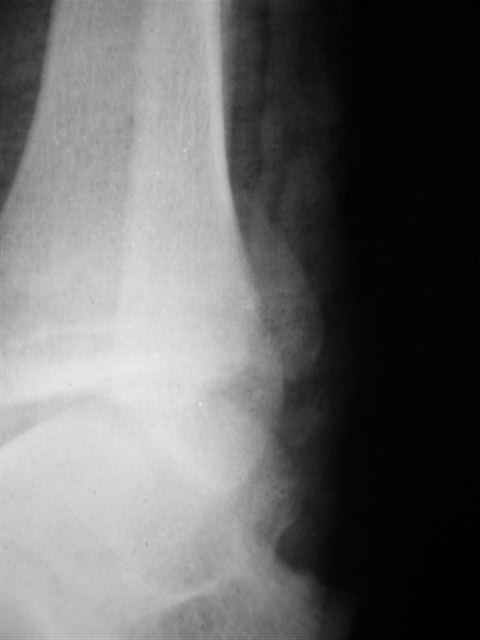

Я предупреждал, что ничего сверхъестественного. Каюсь, что одна из спиц прошла несколько дальше, чем нужно было, но главное - перелом стабилизирован и больной работает суставом в полном объёме, несмотря на представленную раннее травму коленного сустава.

Евгений И Чекашкин